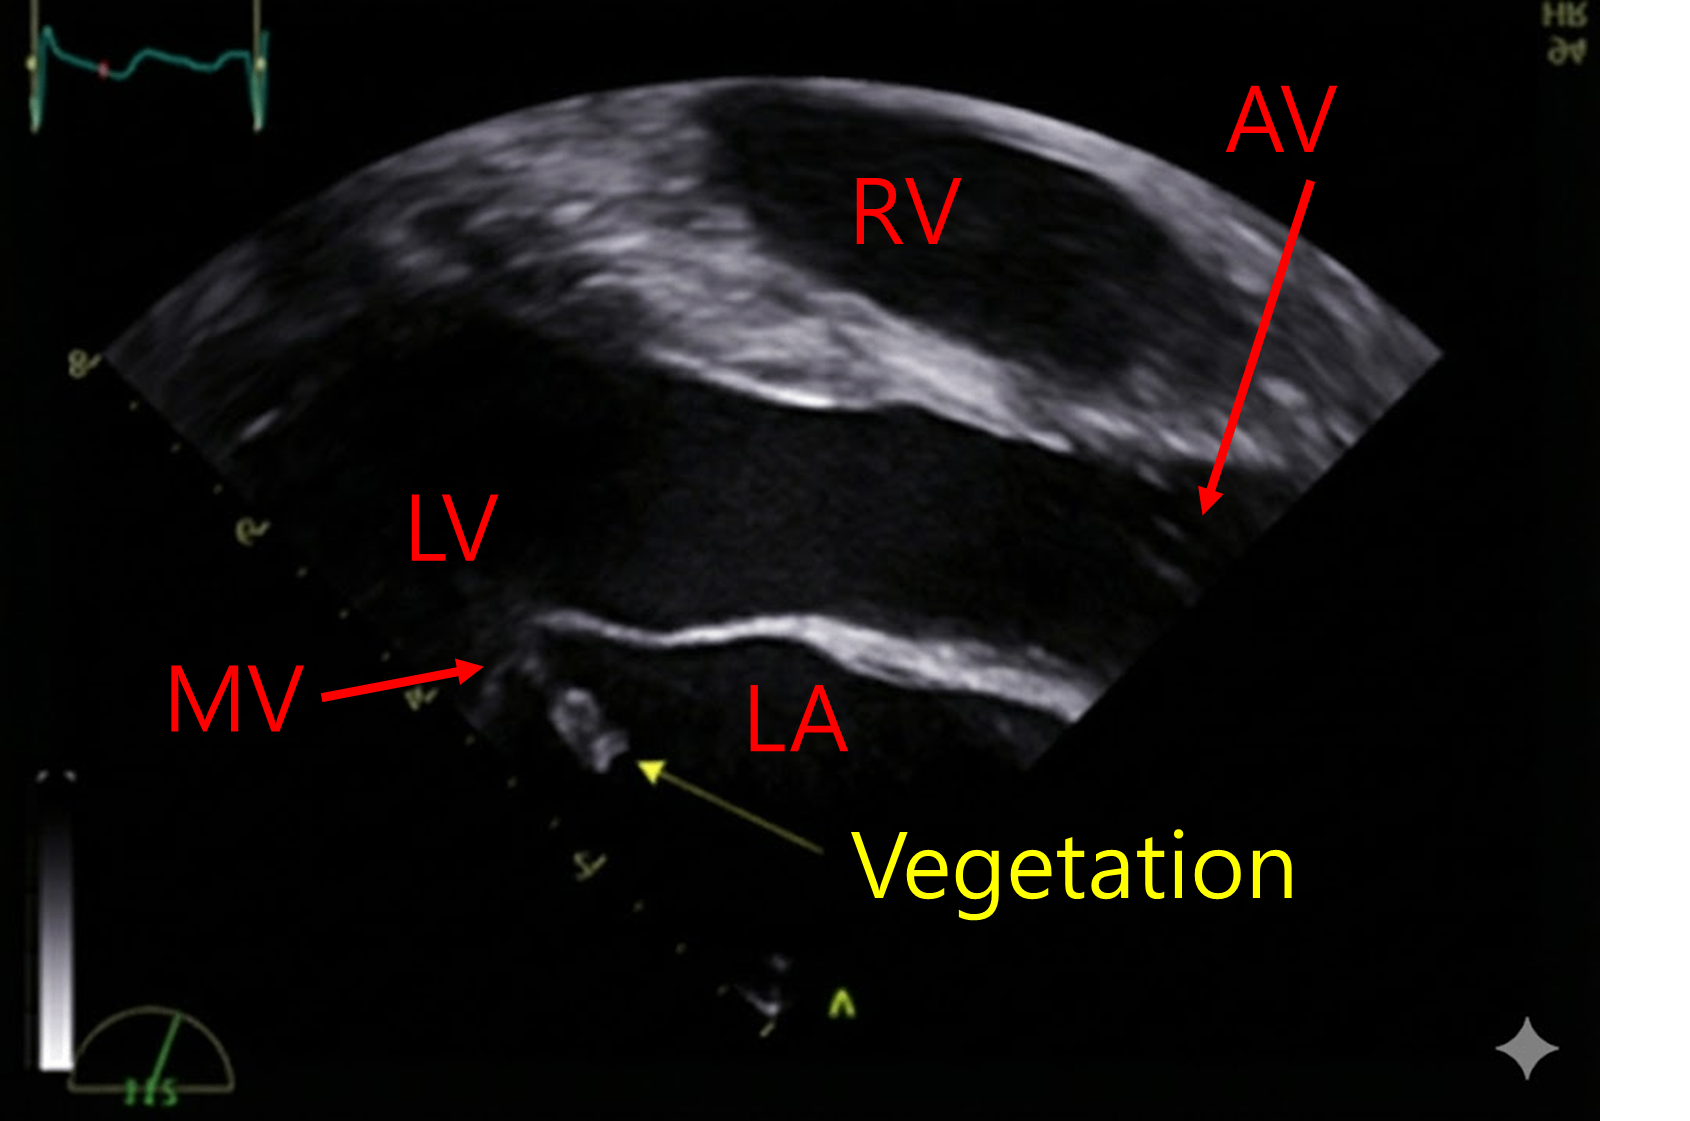

- 심초음파에서 mitral valve에 vegetation 의심소견이 확인된다.

• 평소 익숙한 parasternal long axis view로 상하좌우를 변환하였다. MV에 vegetation이 있는 것을 확인할 수 있다.